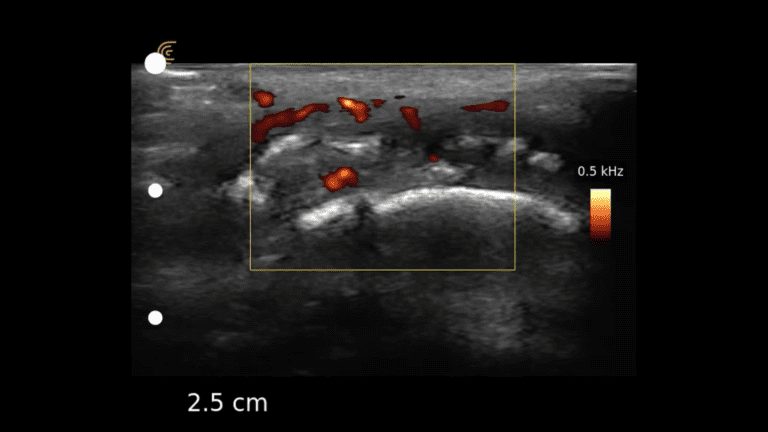

Achilles Tendinopathy Short Axis

Achilles tendon suspicion of active inflammation is confirmed with increase signal using Power Doppler on the area of interest. A normal tendon should have little to no signal.